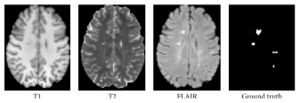

Fully Automated Enhanced Tumor Compartmentalization: Man vs. Machine Reloaded

|

Publication: PLoS One. 2016 Nov 2;11(11):e0165302. PMID: 27806121 | PDF Authors: Porz N, Habegger S, Meier R, Verma R, Jilch A, Fichtner J, Knecht U, Radina C, Schucht P, Beck J, Raabe A, Slotboom J, Reyes M, Wiest R. Institution: Support Center for Advanced Neuroimaging, Institute for Diagnostic and Interventional Neuroradiology, University Hospital and University of Bern, Bern, Switzerland. Background/Purpose: Comparison of a fully-automated segmentation method that uses compartmental volume information to a semi-automatic user-guided and FDA-approved segmentation technique. METHODS: Nineteen patients with a recently diagnosed and histologically confirmed glioblastoma (GBM) were included and MR images were acquired with a 1.5 T MR scanner. Manual segmentation for volumetric analyses was performed using the open source software 3D Slicer version 4.2.2.3. Semi-automatic segmentation was done by four independent neurosurgeons and neuroradiologists using the computer-assisted segmentation tool SmartBrush® (referred to as SB), a semi-automatic user-guided and FDA-approved tumor-outlining program that uses contour expansion. Fully automatic segmentations were performed with the Brain Tumor Image Analysis (BraTumIA, referred to as BT) software. We compared manual (ground truth, referred to as GT), computer-assisted (SB) and fully-automated (BT) segmentations with regard to: (1) products of two maximum diameters for 2D measurements, (2) the Dice coefficient, (3) the positive predictive value, (4) the sensitivity and (5) the volume error. RESULTS: Segmentations by the four expert raters resulted in a mean Dice coefficient between 0.72 and 0.77 using SB. BT achieved a mean Dice coefficient of 0.68. Significant differences were found for intermodal (BT vs. SB) and for intramodal (four SB expert raters) performances. The BT and SB segmentations of the contrast-enhancing volumes achieved a high correlation with the GT. Pearson correlation was 0.8 for BT; however, there were a few discrepancies between raters (BT and SB 1 only). Additional non-enhancing tumor tissue extending the SB volumes was found with BT in 16/19 cases. The clinically motivated sum of products of diameters measure (SPD) revealed neither significant intermodal nor intramodal variations. The analysis time for the four expert raters was faster (1 minute and 47 seconds to 3 minutes and 39 seconds) than with BT (5 minutes). CONCLUSION: BT and SB provide comparable segmentation results in a clinical setting. SB provided similar SPD measures to BT and GT, but differed in the volume analysis in one of the four clinical raters. A major strength of BT may its independence from human interactions, it can thus be employed to handle large datasets and to associate tumor volumes with clinical and/or molecular datasets ("-omics") as well as for clinical analyses of brain tumor compartment volumes as baseline outcome parameters. Due to its multi-compartment segmentation it may provide information about GBM subcompartment compositions that may be subjected to clinical studies to investigate the delineation of the target volumes for adjuvant therapies in the future. |

Set of MRI sequences used in this study for manual, automatic, and semi-automatic tumor volumetry. Original T1-weighted post-contrast MRI slice (A), manual subcompartmental segmentation into non-enhancing tumor (green), enhancing tumor (blue), and necrotic tissue (red) (B). BT subcompartmental segmentation into non-enhancing tumor (green), enhancing tumor (blue) and necrotic tissue (red) (C). BT core tumor segmentation (dark blue, D), SB1 core tumor segmentation (light red, E), SB2 core tumor segmentation (green, F), SB3 core tumor segmentation (purple, G) and SB4 core tumor segmentation (yellow, H). |